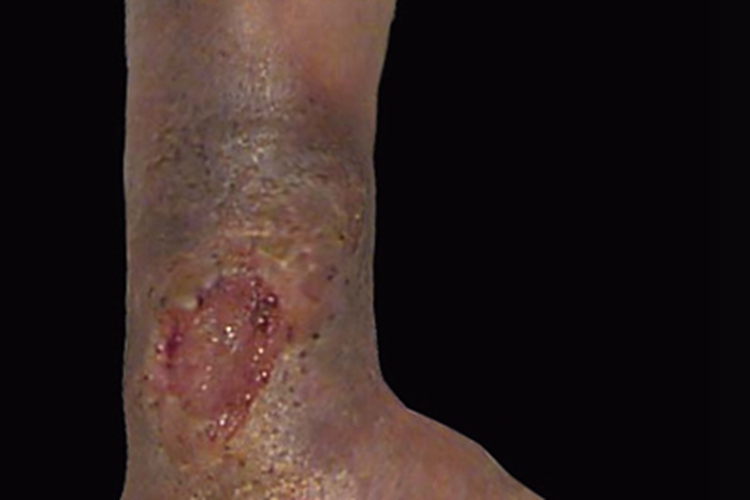

下肢深静脉血栓形成导致的损害可发于部分患者的脚踝,常表现为肿胀、皮色改变等。有时患处可出现溃疡,呈大坑状,还可有周围皮肤发黑、粗糙、干燥等表现。